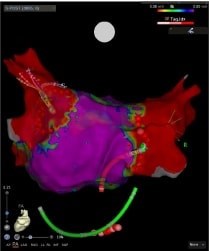

基本となる薬物療法に加えて、当院では高周波カテーテルアブレーションに力を入れています。当院のアブレーションは以下のような点で大きな進歩をしてまいりました。

• 心臓の形態や電位に関する情報をカテーテルを用いて把握

• コンタクトフォース(カテーテルによりかかる力)を可視化し適切な力で焼灼